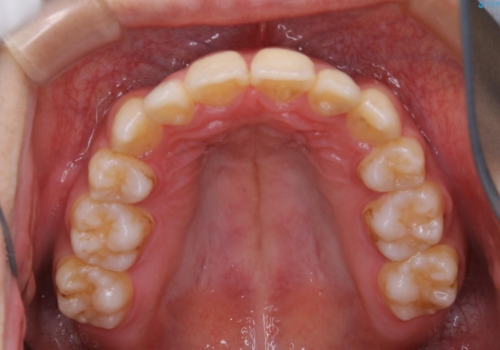

- 元々は海外でワイヤー矯正を行っていたが、コロナ禍で海外への往来が難しくなり、治療を中断せざるを得なくなってしまった方です。

ご本人のご希望により、インビザラインによる治療を行いました。

ブラケット除去直後に目立っていた下顎前歯部の大きなブラックトライアングルもあまり目立たなくなり、大変喜んでいただけました。